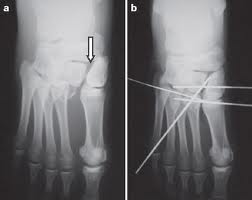

Mid-tarsal dislocation of the first Ray. Closed reduction and K-wire fixation of the first and second tarsometatarsal joints. I snapped my Lisfranc ligament 4 months ago.

What is a joint injury? What is the worst injury you had? K-wires are typically removed after six weeks, before weight bearing, while screws are often removed after 12 weeks. When a Lisfranc injury is characterized by significant displacement of the tarsometatarsal joint snonoperative treatment often leads to severe loss of function and long-term disability secondary to chronic pain and sometimes to a planovalgus deformity.

The base of the second metatarsal is held in place by the plantar TMT ligaments. Closed reduction and percutaneous screw fixation of 1st through 3rd tarsometatarsal joints. Clinical rating systems for the ankle-hind foot, midfoot, hallux and lesser toes. Please vote below and help us build the most advanced adaptive learning platform in medicine The complexity of this topic is appropriate for?